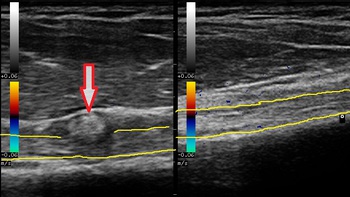

右上腕二頭筋長頭腱 左同部正常側

川越市若葉 60代男性会社員。 肩、腕(うで)の痛み、 上腕二頭筋長頭腱鞘内の腫瘤。

1週間ほど前から右肩を頭上に挙げることが困難となっています。当接骨院の来院時、右肩の

前方の筋肉の痛みが著明であったので超音波検査を実施したところ、右上腕二頭筋長頭腱鞘内に

偶然腫瘤が認められました(左画像の矢印下の丸い腫瘤、黄色い線は左右の上腕二頭筋長頭腱)。

腫瘤を押しても痛みは無いのですが、念のため病院を受診するようお勧めいたしました。